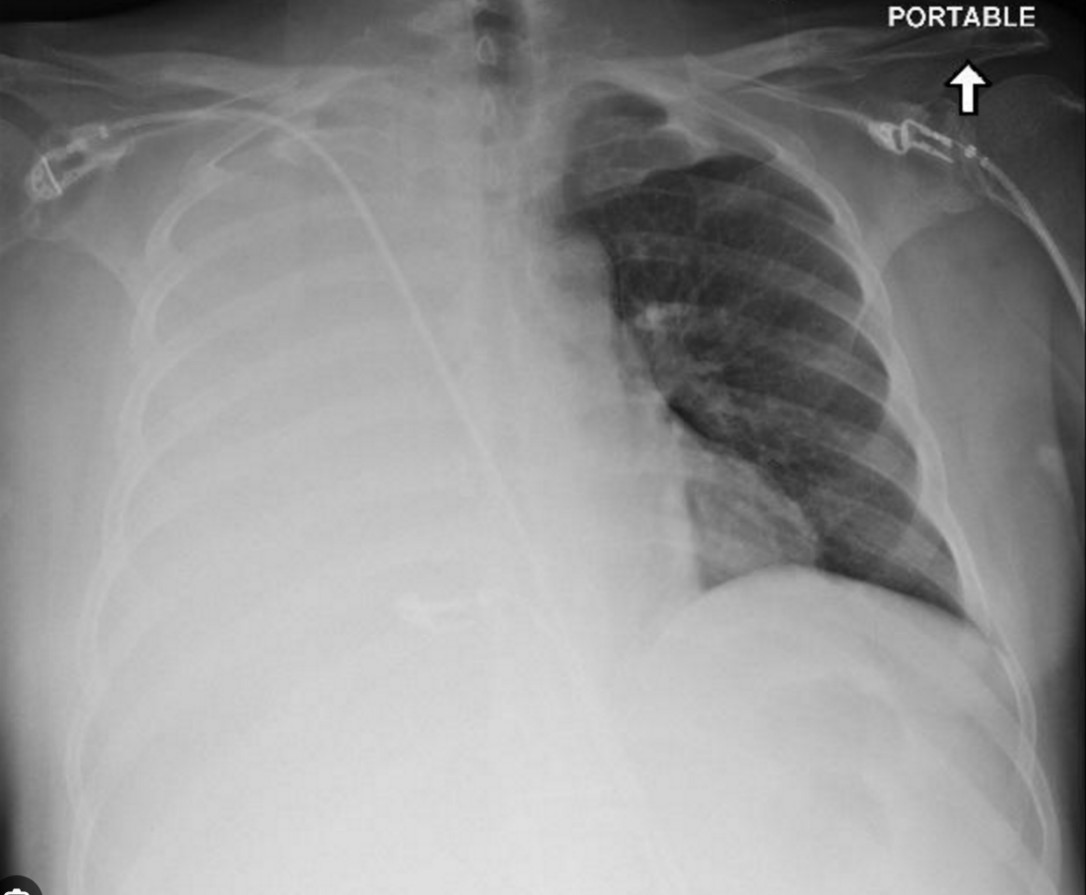

Paediatric blunt chest trauma

You are the resuscitation consultant in a paediatric major trauma centre. A 12-year-old girl is brought in by her parents …